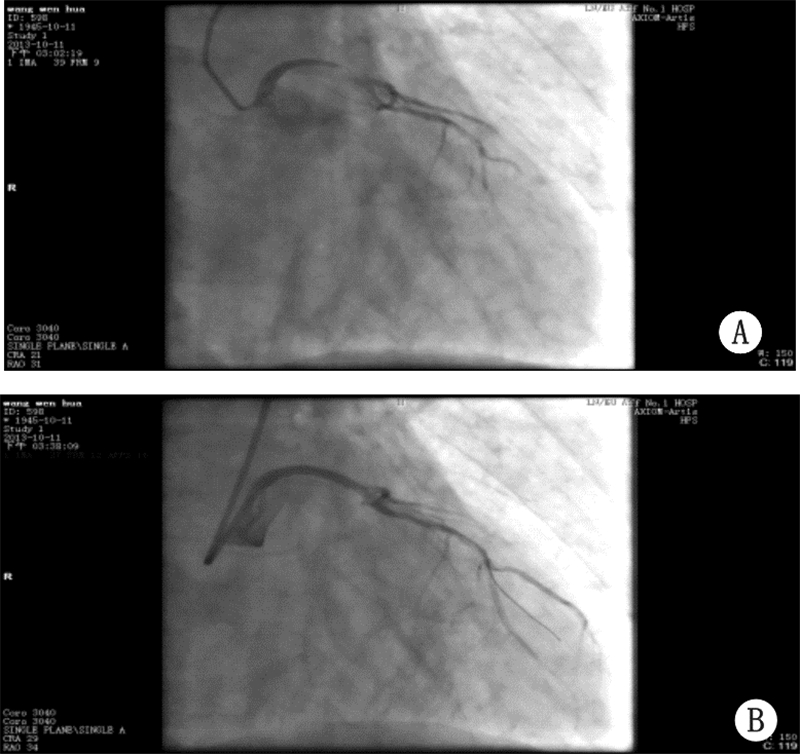

1 资料与方法患者,男,68岁,3年前无明显诱因出现阵发性烧灼样胸骨后疼痛,10~15 min/次,伴有胸闷,气短、大汗,本院诊断为“不稳定性心绞痛”,应用硝酸甘油后症状缓解。此后规律口服阿司匹林、消心痛,上述症状未再发作。入院前3 h无明显诱因出现上述症状,伴有烦躁不安、面色苍白,频繁恶心、呕吐,上腹胀痛,含服硝酸甘油上述症状未缓解。查体:P 54次/min,BP 64/47 mmHg(1 mmHg=0.133 kPa)。面色苍白、皮肤湿冷。神志清,反应迟钝。双肺呼吸音清,未闻及干湿啰音。心率:54次/min,律齐。心电图(图 1A):ST段 aVL导联上抬0.1 mV,Ⅰ、Ⅱ、Ⅲ、aVF、V4-V6导联下移0.1~0.3 mV,aVR导联上移0.2 mV。肌钙蛋白I 27.16 ng/mL。诊断:急性心肌梗死,考虑左主干病变,心源性休克。治疗:常规用药包括:肝素抗凝、可定调脂、多巴胺升压。抗血小板治疗:阿司匹林首剂量300 mg,维持量100 mg/d口服,波立维首剂量600 mg/d,维持量75 mg/d口服;术后常规应用替罗非班静点36 h。急诊冠状动脉造影:左主干末端至左前降支近段95%狭窄,见血栓影,血流TIMI 1级,左回旋支近段100%闭塞,考虑为慢性闭塞,血流TIMI 0级,右冠状动脉弥漫性病变,最窄处50%狭窄,可见侧枝循环向左回旋支供血,血流TIMI 3级(图 2A)。决定行急诊PCI:送6FEBU3.5 指引导管至左冠开口,送Runthrough导丝通过病变处到达前降支远端,再送2.0 mm×15 mm迪马克球囊至前降支至左主干病变处,以12 atm×5″由远至近进行扩张3次,造影示左主干至前降支病变处残余狭窄80%,血流TIMI 2~3级,送乐普3.5 mm×36 mm支架不能通过病变处,送BMW导丝通过病变处,再送乐普3.5 mm×36 mm支架至左主干至前降支病变处,以16 atm×5″进行扩张,释放支架,造影示支架释放满意,无夹层及残余狭窄,血流TIMI 3级(图 2B)。左回旋支病变暂不处理。结果:术后患者胸痛缓解,血压、心率恢复正常。心电图:6 h内aVL导联ST段回降,V3-6导联ST段回到基线(图 1B)。

| 图 2 患者发病时急诊冠状动脉造影结果(A)及 左主干放置支架后造影结果(B) |